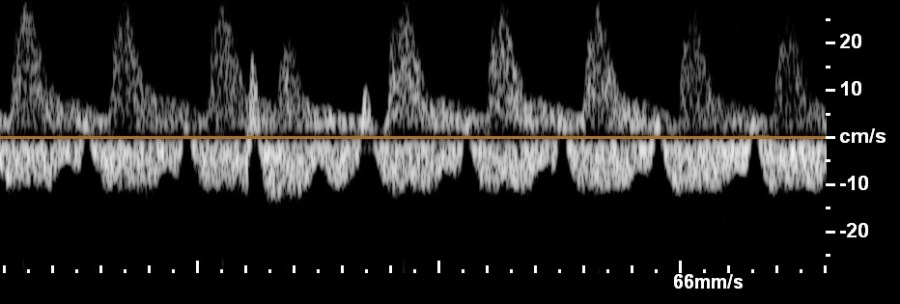

- Doppler velocimetry of the middle cerebral artery to exclude fetal anemia

- fetal hypervolemic heart failure (anemia, arrhythmia, tumor, chorangioma, acceptor fetus of the twin-twin transfusion syndrome, pump twin of the TRAP-sequence),